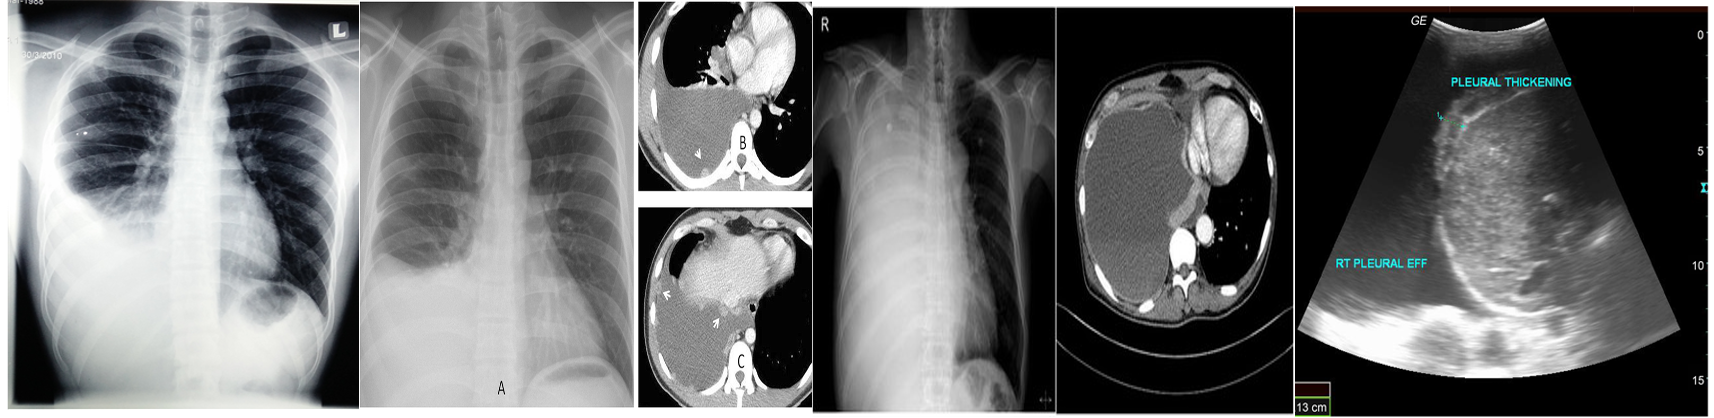

Chest X-ray: Lateral decubitus view (most sensitive): > 200 ml.

- Unilateral blunting of the costophrenic angle

- Homogeneous density with a meniscus-shaped margin (meniscus sign)

- Complete opacification of the lung (Large effusion) and Mediastinal shift and tracheal deviation.

Ultrasound: Quick, bedside assessment, if planning thoracentesis.

- Very sensitive: 20 ml. Hypoechoic collection.

- Detection of pleural thickening and pleural nodules.

CT: Gold standard for small effusions.

- Guiding placement of indwelling pleural catheters.

- Directed thoracentesis of a loculated effusion.

- Suspected parenchymal or pleural pathology. contrast CT is now increasingly performed to investigate the underlying cause, particularly for exudative effusions